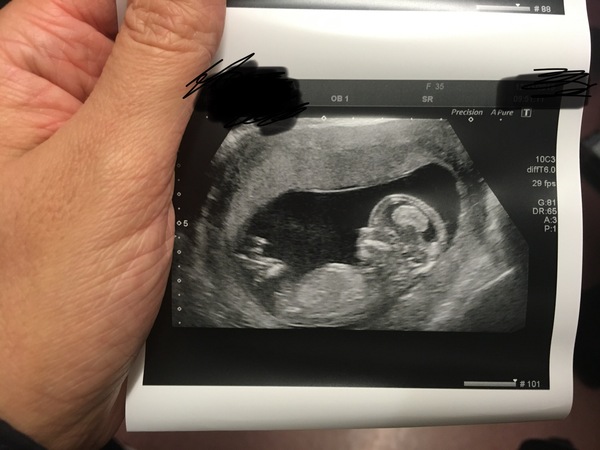

Hi ladies. Happy to report that we had an amazing 12 wk scan. So relieved and excited. Baby was wriggling so much and we saw it kicking it’s legs lots. The relief is immense.

Any guesses on sex ladies? We have our 20wk scan on New Year’s Eve which will be lovely ❤️

Aww @Bumpingalong84 I'm so relieved for you!!!! Yay!!!! I'm going to guess boy, although I have no clue on this theory thing so I'm just going with a feeling 😂 are you going to be finding out? So happy for you. I imagine it was a really anxious time before you went in but instant relief! I had that! Then when I started crying the baby started moving around 😂😂

Aww @mrsf1204 I started crying before I went in, the lady was amazing and reassured me straight away pointing out heartbeat and saying breath, I just had tears rolling down my face. She went through everything and really took her time.

The relief was instant like you say, it’s amazing the weight I felt come off my chest. Telling our DD was equally emotional.

We will be finding out yes 😊 everyone who knows also thinks boy. I’m not sure, but it’s definitely felt different to my pregnancy with DD and less nausea. Either will be amazing but like this guessing game haha, I’m useless at it tho.

@Bumpingalong84 Lovely pic. I'm no good at nub theory but I guess girl.

@Bumpingalong84 gorgeous!! Glad it all went well and that you’re feeling relieved ❤️

@Bumpingalong84 that a beautiful baby image x enjoy

@Bumpingalong84 congratulations on your gorgeous scan photo! I bet you're on cloud nine right now and can't wait to share your amazing news!

The nub isn't overly obvious there but it looks like it is pointing up more then it is parallel so I would guess boy... but that's just my interpretation and I could be wrong! Either way this is clearly one very loved baby already! ❤️